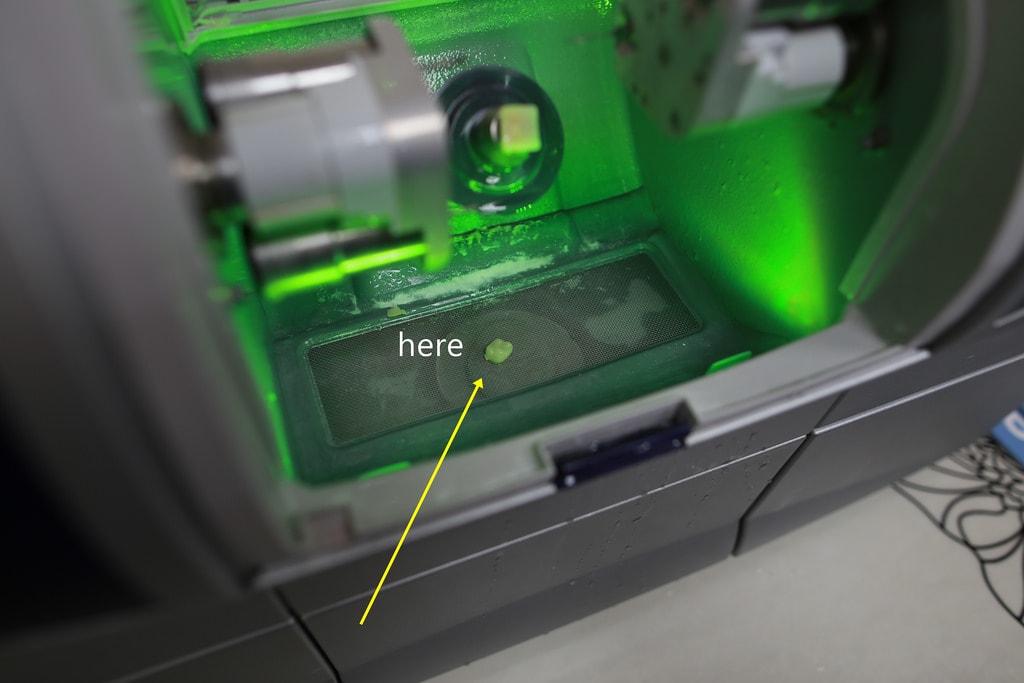

短短時間內就製作完成啦!!

這像不像秀珠寶的感覺(笑)